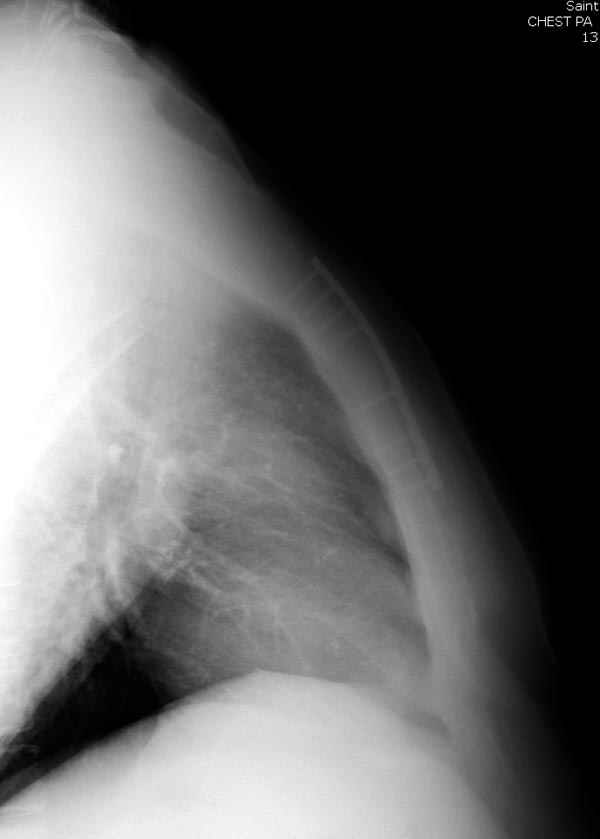

Глубокоуважаемые коллеги, Обратились за советом коллеги из соседней больницы. Мужчина 30 лет, в автоаварии ударился грудью об руль. После травмы 3 недели. Определяется отчетдивая подвижность на месте перелома. Снимок в приложении. Пока обсуждали варианты - LCP (какую?) или спицы. Открывать зону перелома или нет? Что посоветуете?

Пару лет назад коллега из грудной хирургии направил больного с хроническими жалобами на боли по поводу ложного сустава грудины.

Оперировали вместе с грудным хирургом и в нашем случае главной причиной была болезненность. Во время операции приняли все меры предосторожности недопущения прокола средостения (см. на 4 снимке близкий контур сердца!!)

Ложный сустав зафиксирован двумя пластинами 2.4 мм (locking plate) позаимствованными из челюстно-лицевой хирургии, с костной пластикой, все остальные пластины мне показались слишком толстыми, грубые для грудины или отсутсвовали возможности создания угловой стабильности.

Рентген снимки во время операции и последние сделаны на днях.

При переломах грудины со смещением как правило оперируем. В качестве фиксатора используем рекон. LCP, доступ простой, с репозицией проблем не возникало. Для сверла, что бы не провалиться в средостение, используем ограничитель.